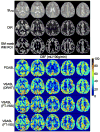

Methods: This new pulse contains paired and phase cycled refocusing pulses. Its sensitivities to B0/B1 inhomogeneity and gradient imperfections such as eddy currents were evaluated through simulation and phantom studies. Cerebral blood flow (CBF) quantification using FT-VSI prepared VSASL was compared with conventional VSASL and pseudocontinuous ASL (PCASL) at 3 Tesla.

Results: Simulation and phantom results of the proposed FT-VSI pulse train demonstrated excellent robustness to B0/B1 field inhomogeneity and eddy currents. The estimated CBF of gray matter and white matter for the FT-VSI prepared VSASL, averaged among eight healthy volunteers, were 49.5 ± 7.5 mL/100 g/min and 14.8 ± 2.4 mL/100 g/min, respectively. Excellent correlation and agreement between the FT-VSI method and conventional VSASL and PCASL were found. The averaged signal-to-noise ratio (SNR) value in gray matter of the FT-VSI method was 39% higher than VSASL using conventional double refocused hyperbolic tangent pulses and 9% lower than PCASL.

Conclusion: A novel FT-VSI pulse train was demonstrated to be a suitable labeling module for VSASL with robustness of velocity-selective profile to B0/B1 field inhomogeneity and gradient imperfections. Compared with conventional VSASL, FT-VSI prepared VSASL produced consistent CBF maps with higher SNR values. Magn Reson Med 76:1136-1148, 2016. © 2015 Wiley Periodicals, Inc.